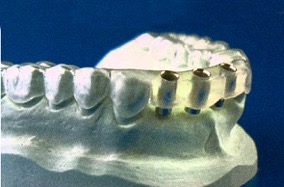

Con un apposito software è possibile pianificare e programmare con massima precisione e scrupolosità l’intervento d’implantologia dentale definendo la dimensione esatta degli impianti rispetto al dente da sostituire e alla conformazione anatomica del paziente. I dati ottenuti da una TAC 3D (un’apparecchiatura radiologica di ultima generazione, in grado di ottenere immagini tridimensionali estremamente dettagliate in pochi secondi, impossibili con qualsiasi altro esame radiografico) vengono trasformati in una mascherina appositamente pre-forata che permette di operare come programmato dal computer. L’intervento diventa meno invasivo poichè l’inserimento degli impianti non necessita di tagli e punti, perciò con trauma minimo, senza gonfiore e dolore. Si possono inserire anche molti impianti in un’unica seduta.